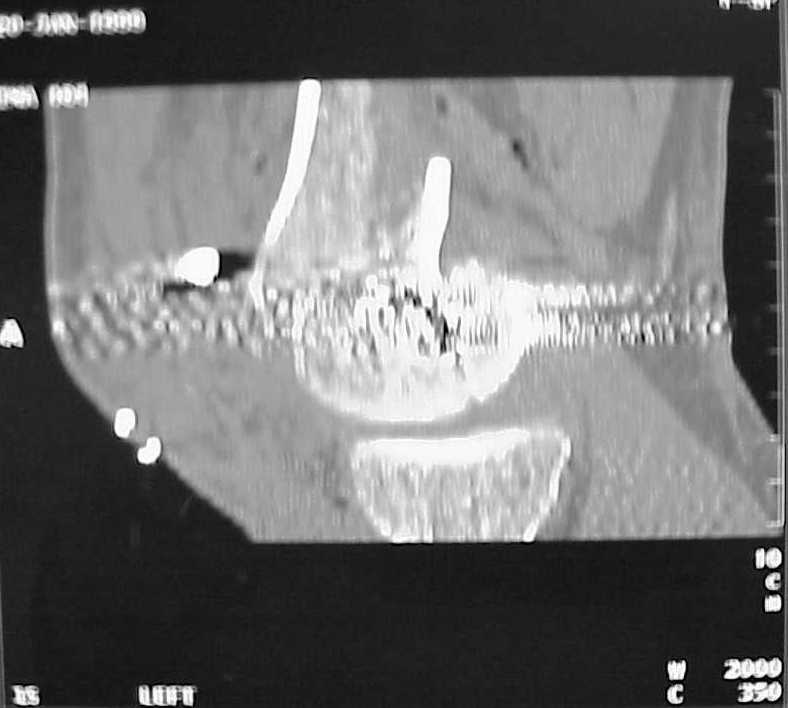

place one anterior to where IMN will go if anterior cortex if insufficient and AP screws on either side of the IMN out of the trochlea to provide some additional varus/valgus stability. I worry about the leg going into valgus w/the lack of lateral cortex.

See attached case that was done several years ago before LISS. He had comminuted trochlea and anterior blocking screws were used to prevent anterior IMN cut-out.